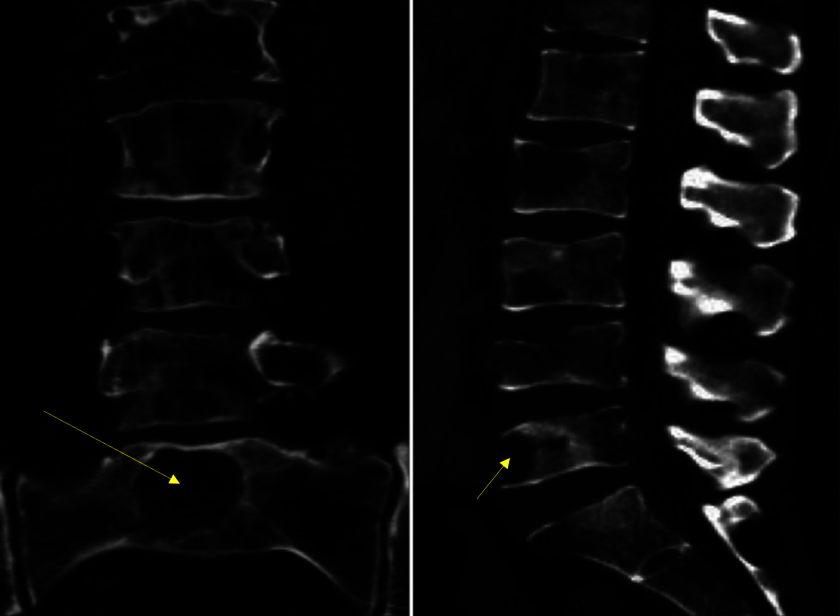

Abbildung 1: Diese seitliche und frontale/ coronare und seitliche Ansicht des unteren Abschnittes der Wirbelsäule zeigt eine Auflösung der Knochenstrukturen (gelbe Pfeile) in allen dargestellten Wirbelkörpern inklusive des Kreuzbeins.

Bis zu 85 Prozent der Patientinnen und Patienten mit Krebserkrankungen leiden an umschriebenen Rückenschmerzen. Die Schmerzen werden häufig durch sogenannte Skelettmetastasen verursacht, also regionale Absiedlungen der Krebserkrankung in den Knochenstrukturen der Wirbelsäule. Die Knochengrundstruktur der Wirbelkörper beginnt sich dadurch aufzulösen, es bilden sich sogenannte Osteolysezonen (Abb. 1). Das kann neben Schmerzen auch dazu führen, dass sich die Form der Wirbelsäule verändert. In diesem Zusammenhang lässt sich manchmal sogar beobachten, dass sich die Körpergröße verkleinert. Die Patienten sacken förmlich in sich zusammen. Zudem beeinträchtigt eine zunehmend aufgelöste Knochenstruktur naturgemäß auch die Stabilitätsfunktion, welche die Wirbelsäule für den menschlichen Körper ausübt.

Mittels Computertomographie oder Magnetresonanztomographie kann man herausfinden, ob und wie stark die Krebserkrankung die Knochenstrukturen der Wirbelsäule zerstört hat (siehe Abbildung 1). Leider wird bei Krebsbefall der Wirbelsäule oft entschieden, dass die Patientinnen und Patienten Bettruhe einhalten, um bewegungsabhängige Schmerzen, aber auch ein Einbrechen der befallenen Wirbel mit etwaigen neurologischen Ausfällen zu vermeiden. Diese Vorsichtsmaßnahme ist heute allerdings nur bedingt empfehlenswert, da sie mit einer weiteren Verschlechterung der Lebensqualität verbunden ist, ohne die Schmerzen grundlegend zu verbessern.